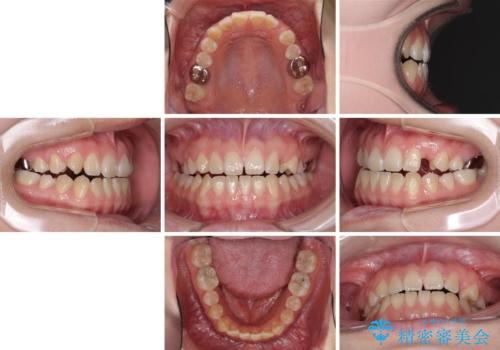

受け口で開咬を急速拡大装置とインビザラインで改善 欠損部分はインプラントにて補綴治療

- 前歯の開咬と、受け口による咬み合わせの悪さを気にして来院された患者様です。

左上は後続永久歯の欠損によりスペースがあり、矯正治療と並行してインプラントあるいはブリッジによる補綴治療が必要な状況でした。

上顎歯列が狭窄していたため、急速拡大装置により上顎骨を側方に拡大し、その後インビザラインにて矯正治療を行うこととしました。

矯正治療と並行してインプラントによる補綴治療を行うこととしました。